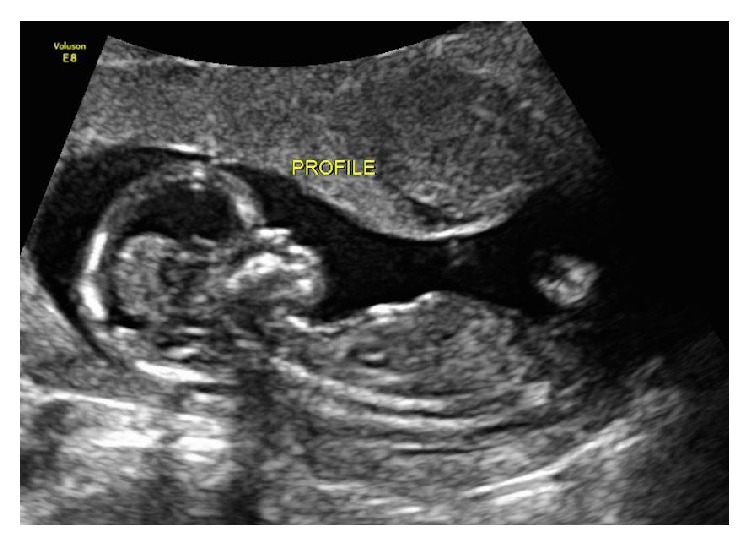

At our initial assessment, other diagnoses associated with nausea and vomiting in pregnancy were excluded: gastroenteritis, hepatitis, appendicitis, pancreatitis, pyelonephritis, and diabetic ketoacidosis. Serum amylase, lipase, liver transaminases, creatinine, and electrolytes were all within normal limits. Urinalysis showed large ketones. At this time, her weight was at its nadir with a loss of 17 kg from her prepregnancy weight (18%). She did not have any other medical comorbidities associated with vitamin K deficiency in pregnancy such as inflammatory bowel disease, celiac disease, bulimia, bariatric surgery, or chronic pancreatitis. She was not taking any warfarin derivatives, vitamin A, or vitamin E. Early anatomy assessment at 14 weeks demonstrated a prominent forehead and flattened facial profile (Figure 1). There was no evidence of bleeding dyscrasias.

Figure 1.

Profile at 14-week gestation shows prominent forehead and nasal hypoplasia.